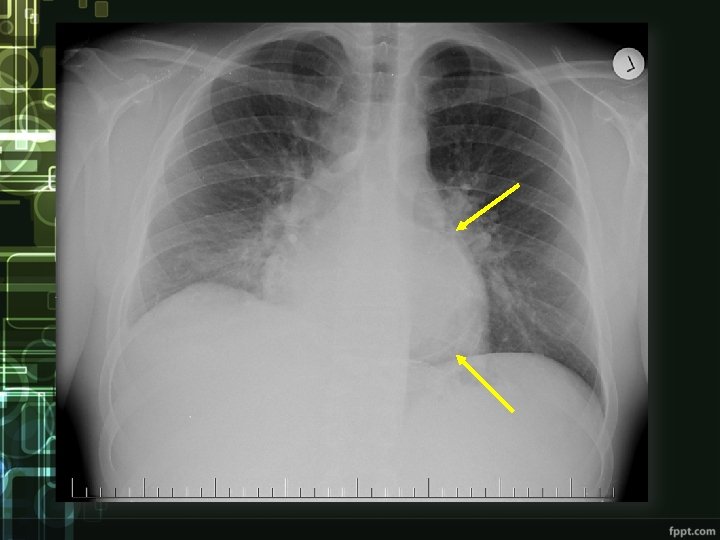

cardiac tamponade